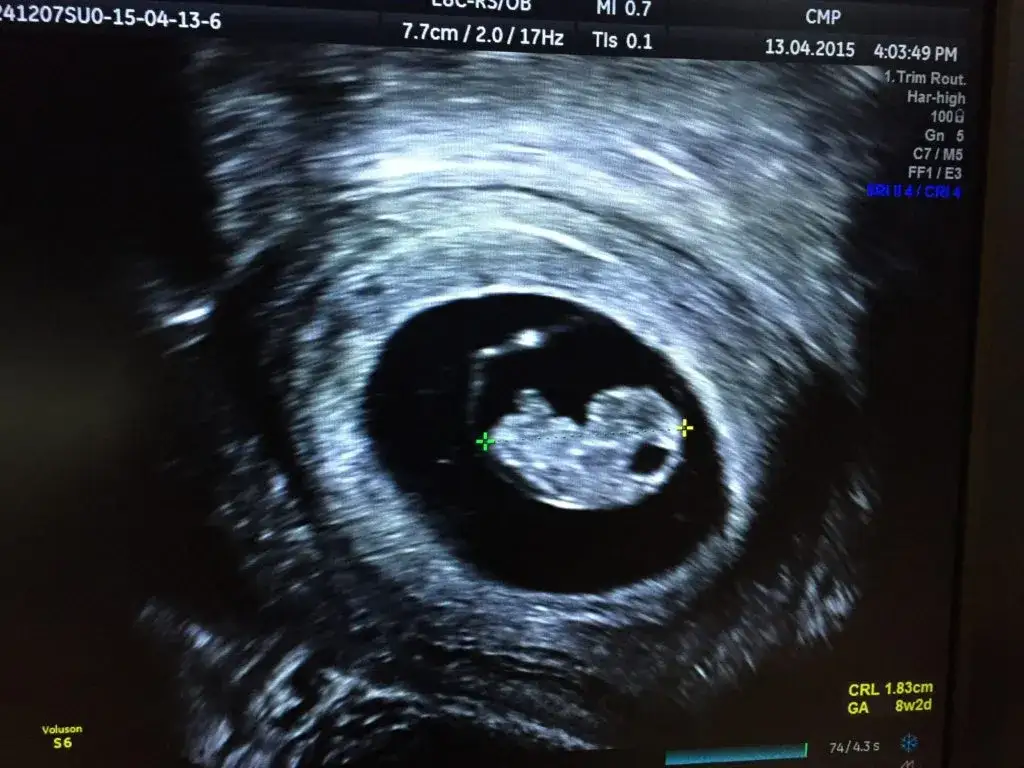

Co lekarz jest w stanie zobaczyć na USG w tym okresie?

- Pęcherzyk ciążowy: Widoczny jako mała, czarna przestrzeń w jamie macicy, świadcząca o obecności ciąży.

- Pęcherzyk żółtkowy: Mała struktura wewnątrz pęcherzyka ciążowego, która dostarcza zarodkowi składników odżywczych na wczesnym etapie.

- Zarodek: Już w 6. tygodniu można zazwyczaj dostrzec maleńki zarodek.

- Czynność serca: Najbardziej wyczekiwany moment! Między 6. a 8. tygodniem ciąży lekarz powinien być w stanie uwidocznić i usłyszeć bijące serce zarodka, co jest kluczowym wskaźnikiem żywej i prawidłowo rozwijającej się ciąży.

Pierwsze USG dopochwowe: chwila, na którą czekasz

Jednym z najbardziej wyczekiwanych momentów pierwszej wizyty jest z pewnością pierwsze USG dopochwowe. Jest ono kluczowe w tym wczesnym etapie ciąży. Służy ono przede wszystkim potwierdzeniu ciąży, ale także ocenie lokalizacji pęcherzyka ciążowego czy zagnieździł się prawidłowo w macicy, czy może poza nią (wykluczenie ciąży pozamacicznej). Dzięki USG mogę również ocenić wielkość zarodka i stwierdzić czynność serca, co jest najważniejszym potwierdzeniem żywej ciąży. To właśnie na tym badaniu często po raz pierwszy widzicie swoje maleństwo, choć jeszcze bardzo malutkie.